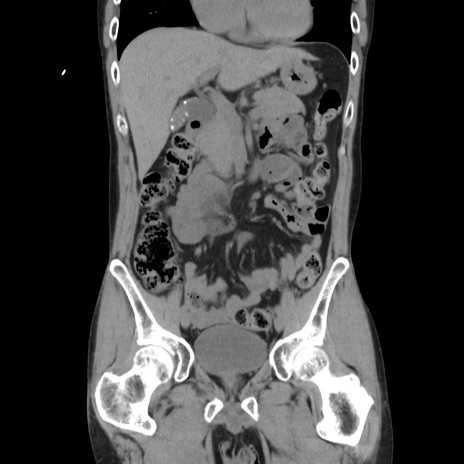

症例37(冠状断像)

【症例】40歳代 男性

【主訴】腹痛

【現病歴】4時間ほど前に電車に乗車中に臍部上より腹痛出現。徐々に増悪し起立困難となり、救急外来受診。生ものは数日食べていない。今朝お雑煮を食べた。

【身体所見】BT 36.8℃、BP 117/84mmHg、HR 91/min、SpO2 97%、苦悶様、腹部:臍上部広範囲圧痛あり、反跳痛±

【データ】WBC 8100、CRP 0.03